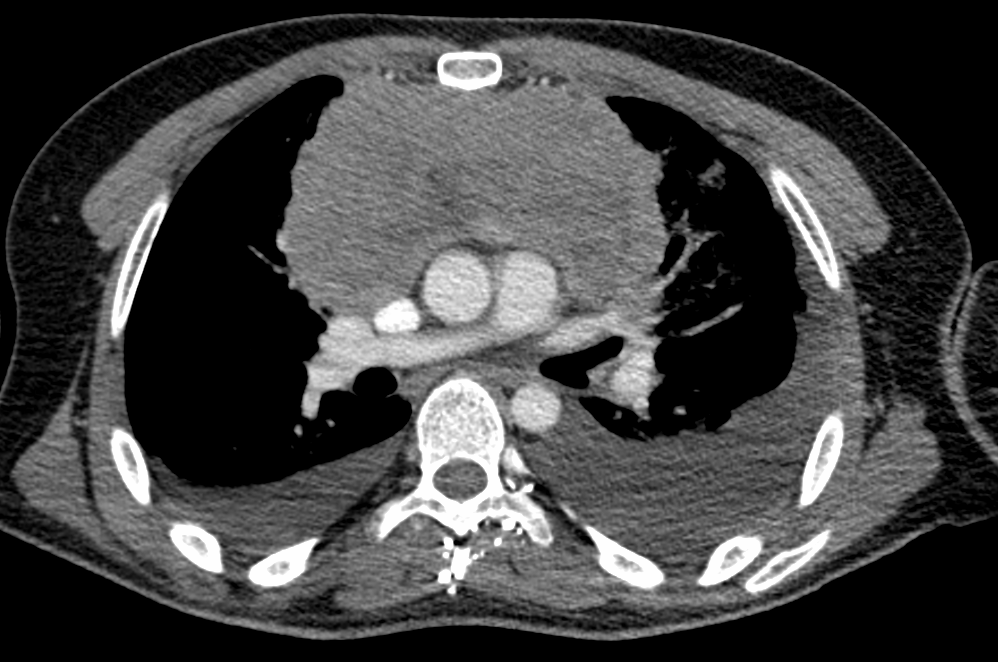

Biopsia de mediastino anterior 2